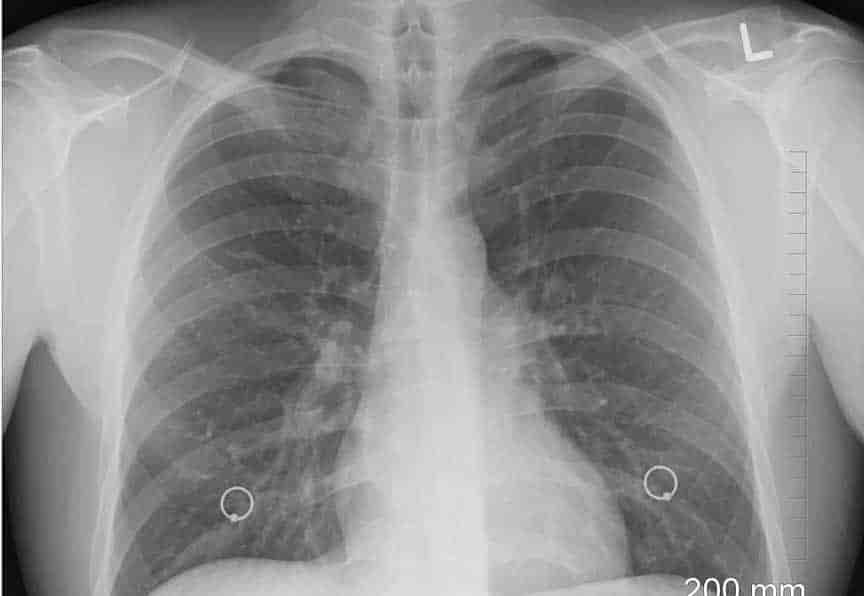

"Todavía hay personas que dicen 'Estoy bien. No tengo ningún problema', y cuando les haces una radiografía de tórax, absolutamente tienen una radiografía de tórax mala", dijo.

Aunado a lo anterior comentó que se pueden ver a través de los estudios líneas blancas que son indicios de cicatrización y congestión en todo el mundo. "El hecho de que eso esté en una radiografía de tu tórax - es indicativo de que posiblemente tengas problemas más adelante".